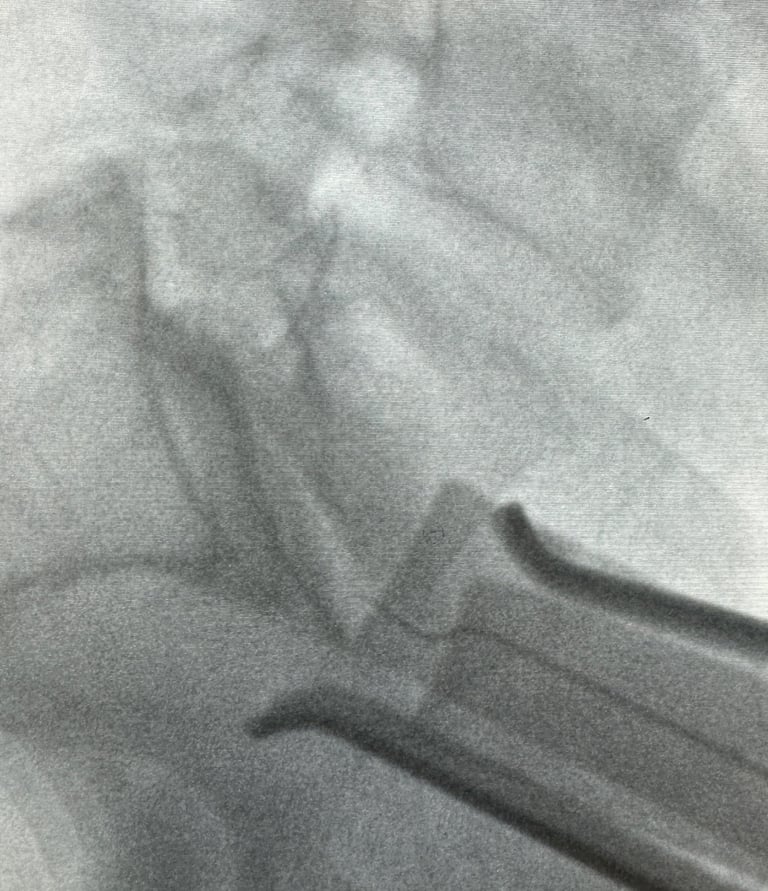

Precision in lumbar spine surgical exposures with prospective data analysis to optimize surgical outcomes

Snapshots of precision in lumbar spine imaging

Precision Imaging

Delivering clear, detailed spinal exposures.